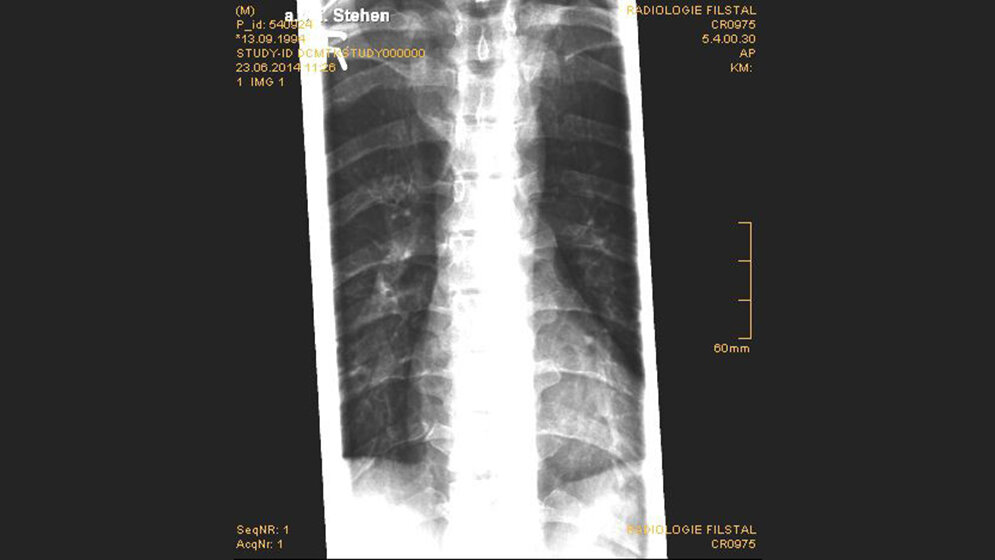

Traumatische Veränderungen: Frakturen der Wirbelfortsätze

Abhängig von der Art und dem Ausmaß der Gewalteinwirkung können die traumatischen Läsionen der Wirbelsäule sehr unterschiedlich sein und ohne oder mit neurologischen Störungen einhergehen.

Patienten mit einem stumpfen Thoraxtrauma sollten zeitnah radiologisch untersucht werden, um adäquate Therapiemaßnahmen einleiten zu können. CT und MRT sind die wesentlichen Arbeitsmethoden der Wirbelsäulentraumaradiologie.